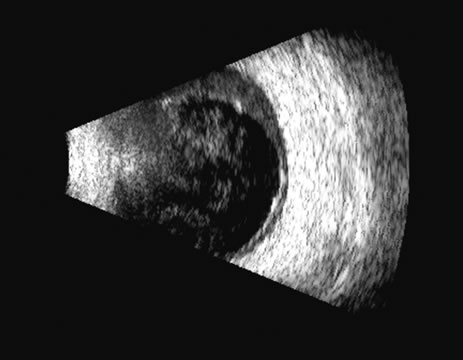

There are several tumors that invade the vitreous or the vitreous space. In

calcium, which is very reflective (Fig. 20). Malignant melanoma, hemangioma, metastatic carcinoma, and subretinal

Malignant melanoma varies in its ultrasound presentation from a relatively homogeneous to heterogenous lesion on B-scan. The typical uveal melanoma absorbs sound so that the posterior section is relatively less echoic than the anterior aspect, producing a gradually decreasing amplitude, often to baseline on the A-scan (Fig. 21).

Melanomas also have varying amounts of melanin, a highly acoustically reflective pigment. As noted, melanomas characteristically show high reflectivity anteriorly, with decreasing reflectance as the sound traverses the tissue. This produces the decreasing amplitude posteriorly in the tumor seen on A-scan and gray-scale B-scan. This effect often enhances the anterior scleral boundary. The posterior tumor border is thus measured as the first “rising” echo from the tumor decline, and it is most easily seen and accurately identified on B-scan.27 Metastatic carcinoma is more heterogeneous, producing a more uniform A-scan amplitude of roughly 50% to 80% of the “scleral” echo amplitude (see below) behind the tumor (Fig. 22). Hemangioma is a very highly reflective tumor with high amplitude all the way through the tumor of 80% to 100% of scleral echo amplitude (Fig. 23). The differentiation of tumor tissues is made possible by differences in cellular organization and concentration.29 Acoustically, these are termed as differences in backscattering properties.30–32 A homogeneous solid tissue, such as the lens or the optic nerve, may present few or no echogenic discontinuities and thus appear anechoic and cyst-like. (An echogenic discontinuity is technically an acoustic impedance mismatch in which the acoustic impedance is the product of the density and the speed of sound in each tissue.) A fluid–smooth tissue boundary has a high mismatch or discontinuity and thus produces a high-amplitude echo. A hemangioma with alternating blood- and tissue-lined sacs thus produces a solid-appearing tissue with high-amplitude echoes seen at all depths of the tissue. A metastatic tumor is nearly always a very heterogeneous tissue with randomly organized clumps of similar cells bounded by strands of vessels, necrotic areas, and connective tissue, thus producing a pattern of moderately high-amplitude sustained echoes. To provide a meaningful, reproducible standard of comparison, we use the scleral echo—that is, an echo behind the tumor—for comparison. We believe that the scleral echo generally is highest at the posterior sclera–Tenon's boundary; whereas Ossoinig has stated that the high amplitude echo is at the anterior scleral boundary.28,33 This school (standardized echography) also recommends a tissue velocity for melanoma of 1550 m/sec34,35 compared with the value of 1660 m/sec that we recommend. These differences can produce significant variations in measurement of tumor height, depending on the interpretive methodology used. The velocity of 1550 m/sec gives a smaller tumor height than that of 1660 m/sec, wheras the inclusion of scleral thickness may add 1 to 2 mm to the tumor height when standard echography is used. While this does not affect comparisons of tumor growth, it has a significant bearing on comparisons of data from various investigators.27 On B-scan, the invasion or replacement of the choroid by tumor is of diagnostic importance. Subretinal hemorrhage rests on a smooth curve of the posterior poles; whereas melanoma may replace the choroid, producing an “excavated” pattern.36 A completely dislocated lens can also emulate a tumor but can be differentiated by clinical findings and by having the patient move his or her eye during the examination, which causes lens displacement (Fig. 24).